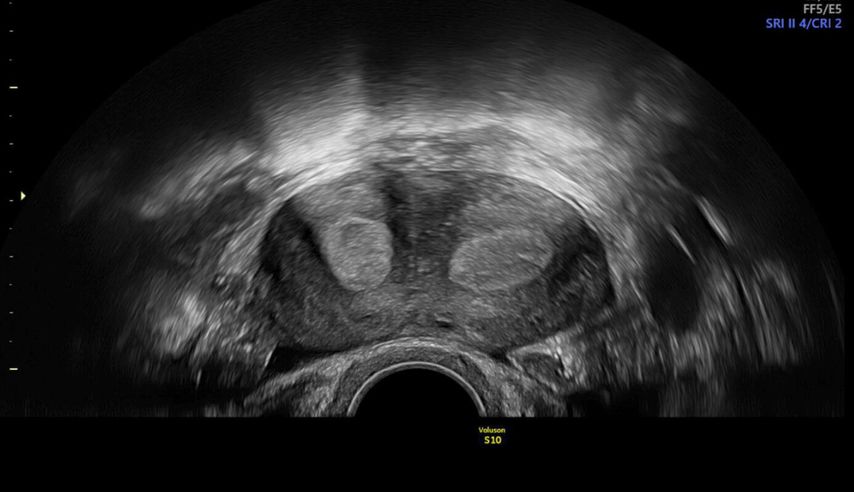

Die Untersuchung wird idealerweise bei hoch aufgebautem Endometrium durchgeführt. Nach Erstellung der Koronarebene kann sowohl die äussere als auch die innere Uteruskontur dargestellt und die Fundusdicke («fundal thickness», FTH) bestimmt werden (Abb. 2). Eine allfällige Septierung ist dabei einfach erkennbar und mittels eines Messkreuzes leicht objektivierbar. Dies lässt sich einfach konstruieren: Zunächst wird eine Hilfslinie zwischen den beiden inneren Tubenostien eingezeichnet (sog. Interostiallinie). Nun kann kranial davon die Fundusdicke (bis zur Serosa) und kaudal davon die Länge des Septums sowie der Winkel der Septumspitze bzw. Carina ausgemessen werden (Abb. 3). Je nach Klassifikationssystem unterscheiden sich hier die Definitionen bzw. Massangaben, welche zur Diagnose einer Fehlbildung nötig sind. Während die ESHRE-ESGE-Guideline relativ «laxe» Kriterien vorschlägt, unter deren Anwendung viele Patientinnen die Diagnose eines Uterus (sub-)septus erhalten würden (bis zu 80%!), landen gemäss ASRM-Klassifikation viele Patientinnen in einer «Grauzone». Hier bewähren sich die CUME-Kriterien, mit deren Hilfe eine Einteilung gelingt, die am ehesten der tatsächlichen Prävalenz entspricht, und dies bei entsprechender Trennschärfe.8 Die vorgeschlagenen Kriterien zur Diagnose eines Uterusseptums sind eine Septumlänge von mindestens 10 mm, ein Winkel von <140° und ein Verhältnis Septum:Fundusdicke von >110% (Abb. 4, Tab. 1).

Abb. 3: Ausmessen der Septumlänge. Nach Anlegen der Interostiallinie (grau) zwischen den Tubenostien können die Fundusdicke und das Septum (innere Einkerbung, engl. «indentation») ausgemessen werden. Nicht eingezeichnet ist hier die Messung des Septumwinkels

Abb. 2: Multiplanare Rekonstruktion der Koronarebene. Die äussere und innere Funduskontur sind rot eingezeichnet. Die Fundusdicke («fundal thickness», FTH) lässt sich ausmessen